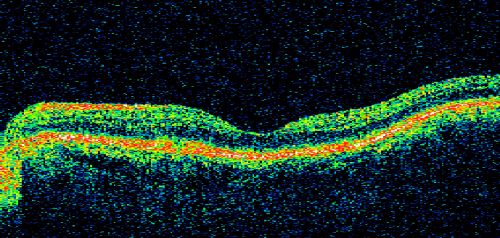

Patterned Pigment Dystrophy of the Fovea 79 YO Woman VA 20/20 Right 20/30 Left

Pattern Dystrophy - Butterfly (Group 2)